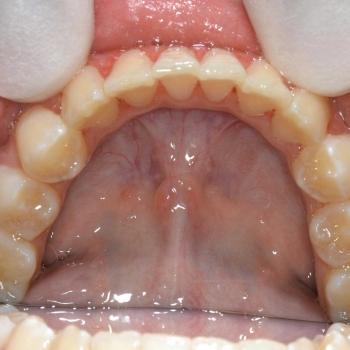

Kíra és édesanyja egy kollegám javaslatára kerestek fel a rögzített fogszabályzó számára legoptimálisabb időszakban, a tejfogak leváltása után, de még a 7-es fog előtörése előtt. Az első konzultáció alkalmával fény derült az alsó és felső fogív nagymértékű torlódására, a jobb felső szemfog kiszorult helyzetére és következményes felső középvonal eltolódására, illetve az enyhe mélyharapásra. A röntgenek kiértékelése után ez a kórkép kiegészült az alsó és felső metszőfogak hátradőlt pozíciójával, ami a kezelést nagyban megkönnyítette, mert lehetőséget adott mindkét fogív meghosszabbítására, így helynyerésre a torlódott fogazat számára.

Ennek megfelelően a kezelés kizárólag alsó és felső hagyományos fém fogszabályozót tartalmazott bite turbo harapásemeléssel kiegészítve, illetve a harapás finombeállításához különböző intermaxilláris gumihúzásokkal.

A kezelés megoldotta az összes fogszabályozással kapcsolatos problémát, így egy funkcionálisan és esztétikailag is megfelelő harapást kaptunk.

A kezelés teljes időtartama: 2 év